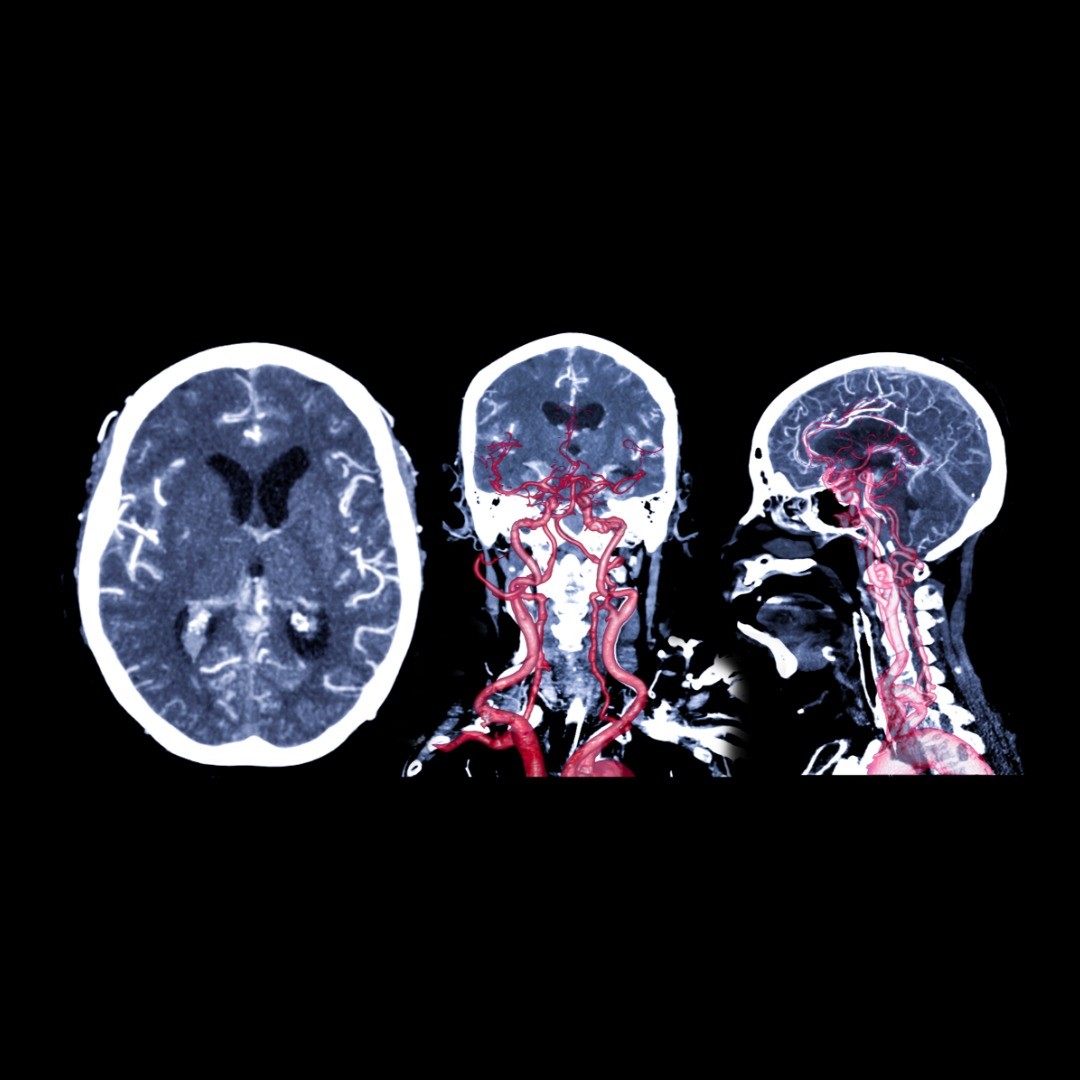

Under general anesthesia, an incision is made in the scalp. A craniotomy is a procedure that temporarily removes a small portion of the skull, by first drilling small burr holes to allow a special surgical instrument to create a bone flap. The bone flap is extracted and the dura mater is exposed.

Retractors carefully nudge the brain so the neurosurgeon can pinpoint the aneurysm. Once control of the blood flow to the aneurysm is obtained and the base of the aneurysm is freed from surrounding tissues, an aneurysm clip, typically titanium, is applied to constrict blood flow from the artery to the aneurysm.

The surgeon verifies that the clip is preventing blood to supply the aneurysm. The retractors are withdrawn and the dura mater is sutured shut. The bone flap is reattached with plates and screws, and muscles and skin are also sutured closed.